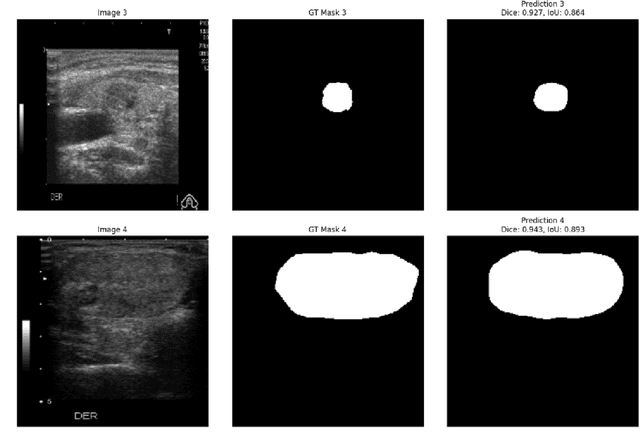

Abstract:Ultrasound-based risk stratification of thyroid nodules is a critical clinical task, but it suffers from high inter-observer variability. While many deep learning (DL) models function as "black boxes," we propose a fully automated, two-stage framework for interpretable malignancy prediction. Our method achieves interpretability by forcing the model to focus only on clinically relevant regions. First, a TransUNet model automatically segments the thyroid nodule. The resulting mask is then used to create a region of interest around the nodule, and this localised image is fed directly into a ResNet-18 classifier. We evaluated our framework using 5-fold cross-validation on a clinical dataset of 349 images, where it achieved a high F1-score of 0.852 for predicting malignancy. To validate its performance, we compared it against a strong baseline using a Random Forest classifier with hand-crafted morphological features, which achieved an F1-score of 0.829. The superior performance of our DL framework suggests that the implicit visual features learned from the localised nodule are more predictive than explicit shape features alone. This is the first fully automated end-to-end pipeline for both detecting thyroid nodules on ultrasound images and predicting their malignancy.